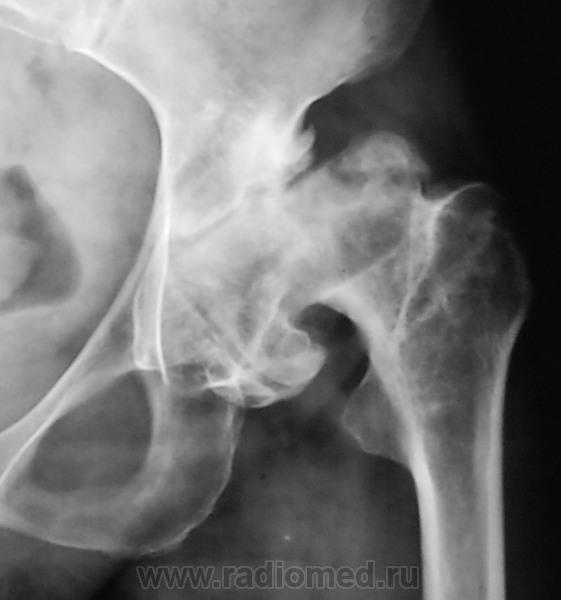

Анкилоз левого ТБС?

Каков же анамнез заболевания,  со стороны левого тазобедренного сустава ?

Думаю, слева не анкилоз, а активно пользуемый диспластический коксартроз. Справа за счет дефицита костной массы впадины зафрезевали чашку глубоко: бедро высоковато стоит, если сравнивать с нормой. Однако же все подлиннее, нежели левая нога.